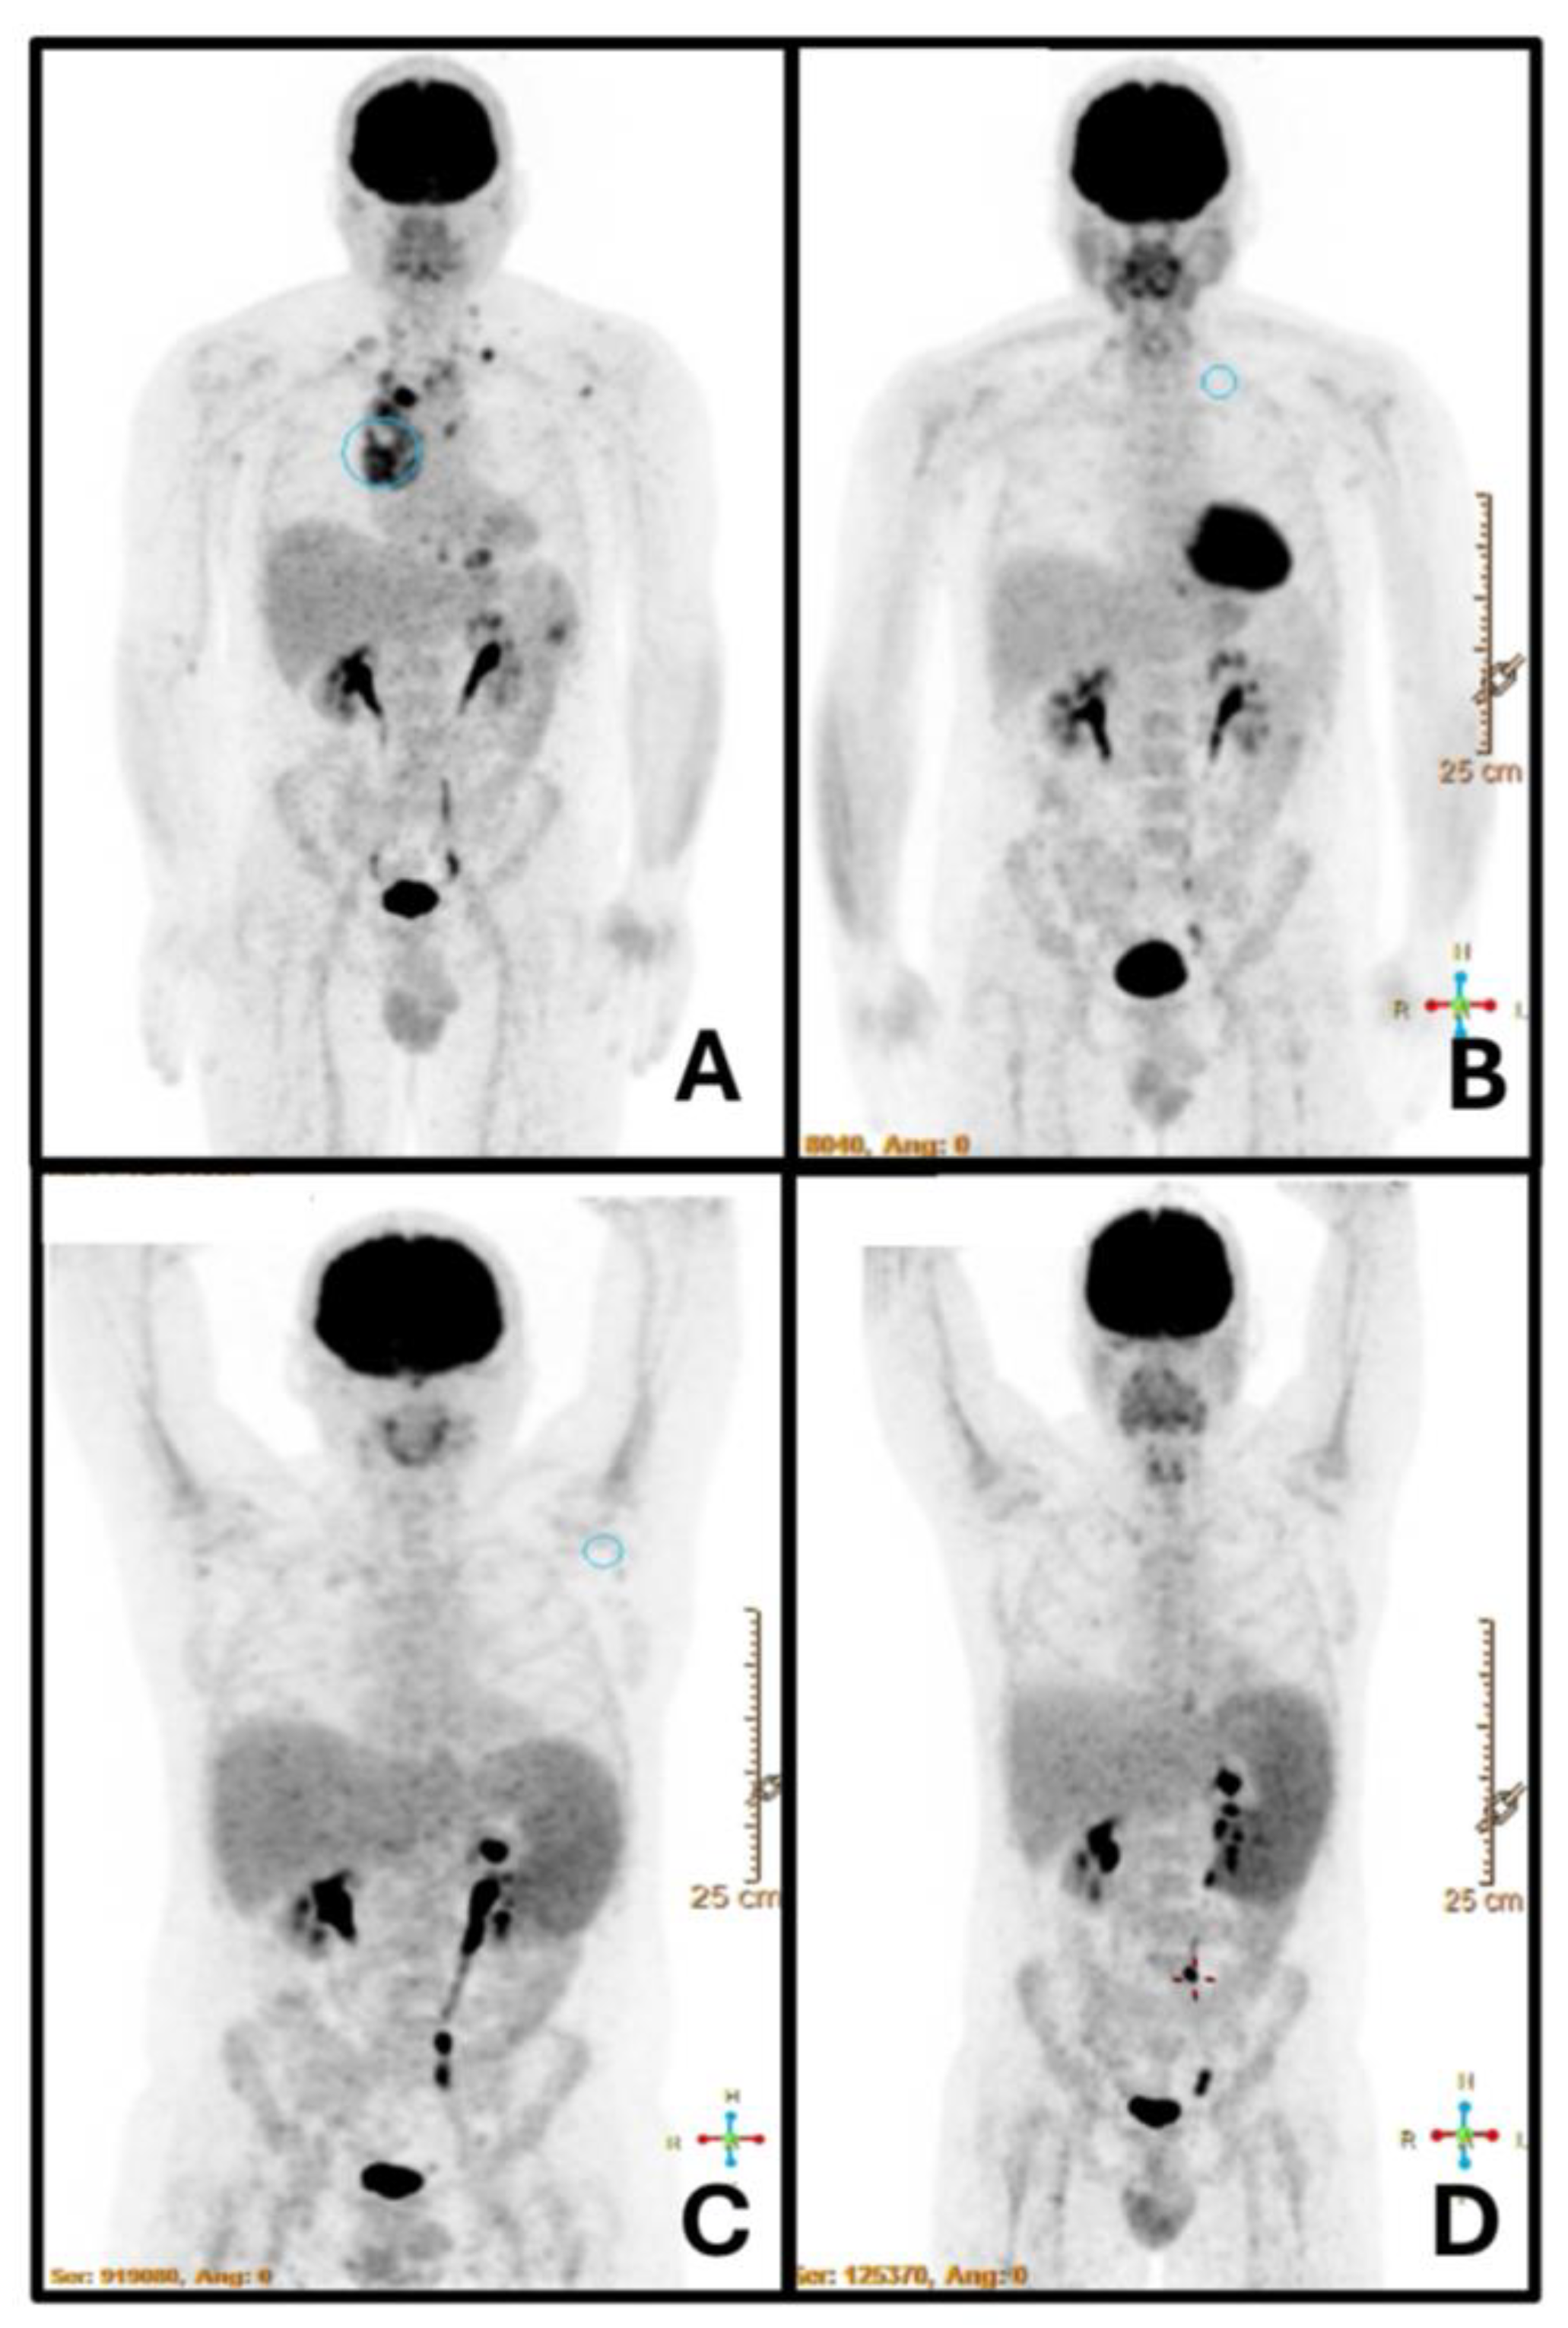

- Pinnegar, H.P.; Sánchez-Montalvá, A.; Profitos, M.B.; Bosch-Nicolau, P.; Salvador, F.; Molina, I. Utility of Fluorine-18 Fluorodeoxyglucose Positron Emission Tomography/Computed Tomography in Patients with Visceral Leishmaniasis: Case Report and Literature Review. Am. J. Trop. Med. Hyg. 2021, 104, 934–944. [CrossRef]